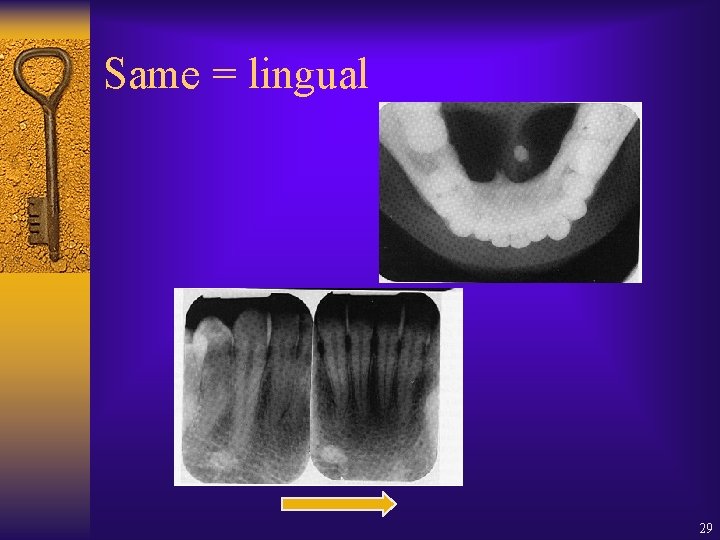

Same = lingual 29